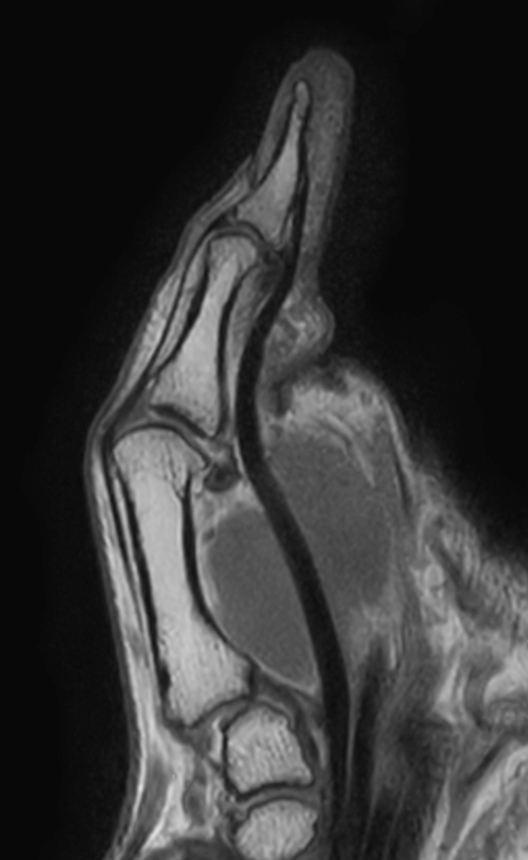

Patient with pathology on the thumb. ExamCard includes mDIXON XD TSE to achieve uniform, complete and consistent fat-free imaging. It simplifies the scan procedure by providing multiple image types in one single scan, including with/without fat suppression contrasts.

Sagittal T1w TSE